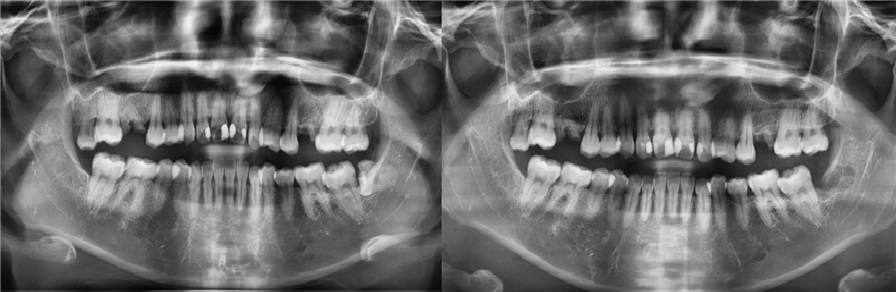

치료전후사진